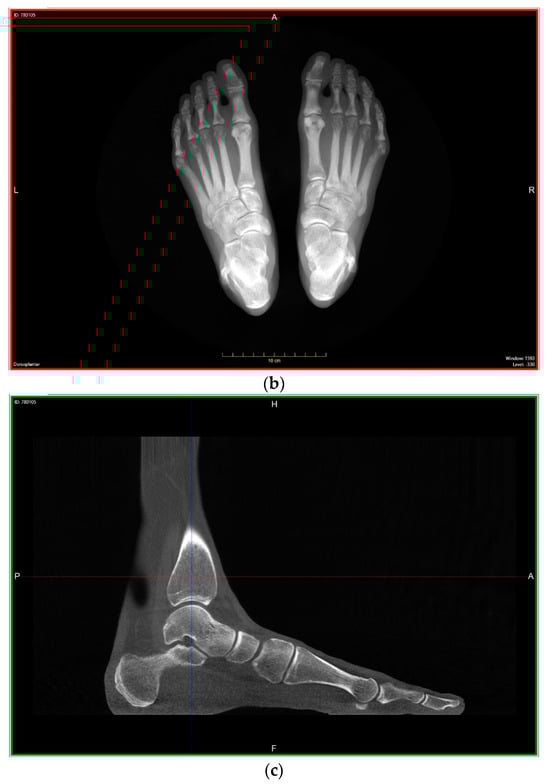

4.2.1. Description of Techniques for Image Acquisition

4.2.2. Description of Advanced Computerized Techniques for Image Processing